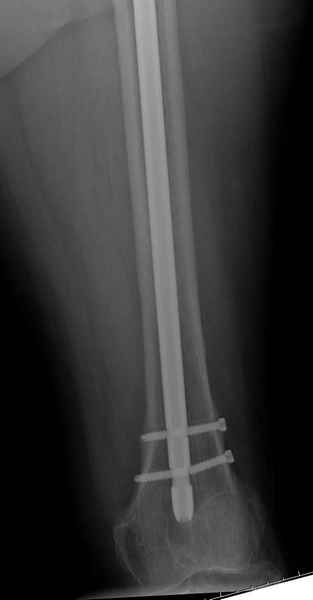

Михаил, здравствуйте. Если присмотреться - на четвертом снимке есть перелом гвоздя по отверстию.

Не стали усложнять интрамедуллярным вариантом коррекции, легче контролировать коррекцию пластиной, поэтому сделали операцию 95 градусной Blade Plate, разогнув до 110 градусов.

Надеемся на успех, потому что до введения пластины дефект от импланта забили костной стружкой и удалось создать компрессию между отломками, максимальную для импланта (150 кило/паунд). Сделана дополнительная костная пластика и за счет измененного угла пластины устранено укорочение конечности.

Страйкер предоставил отличный инструмент - крючок для удаления длинного гвоздя. Считаем, что врачебная ошибка по установке привела к несостоятельности импланта и к ятрогенному осложнению.